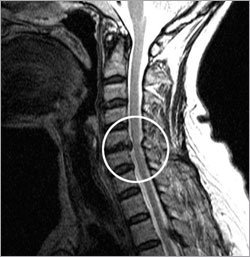

목디스크란 목뼈 사이에 있는 디스크가 손상되어 신경을 압박하는 질환을 의미합니다. 디스크는 젤리와 같은 수핵과 섬유륜으로 구성되어 있습니다. 섬유륜이 손상되면 수핵이 밖으로 밀려나와 신경을 압박하게 됩니다.